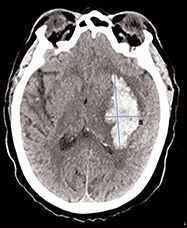

Urgent warfarin reversal in action

Connect live with a healthcare professional to explore case scenarios requiring warfarin reversal for patients with acute major bleeding or in need of urgent surgery/invasive procedures